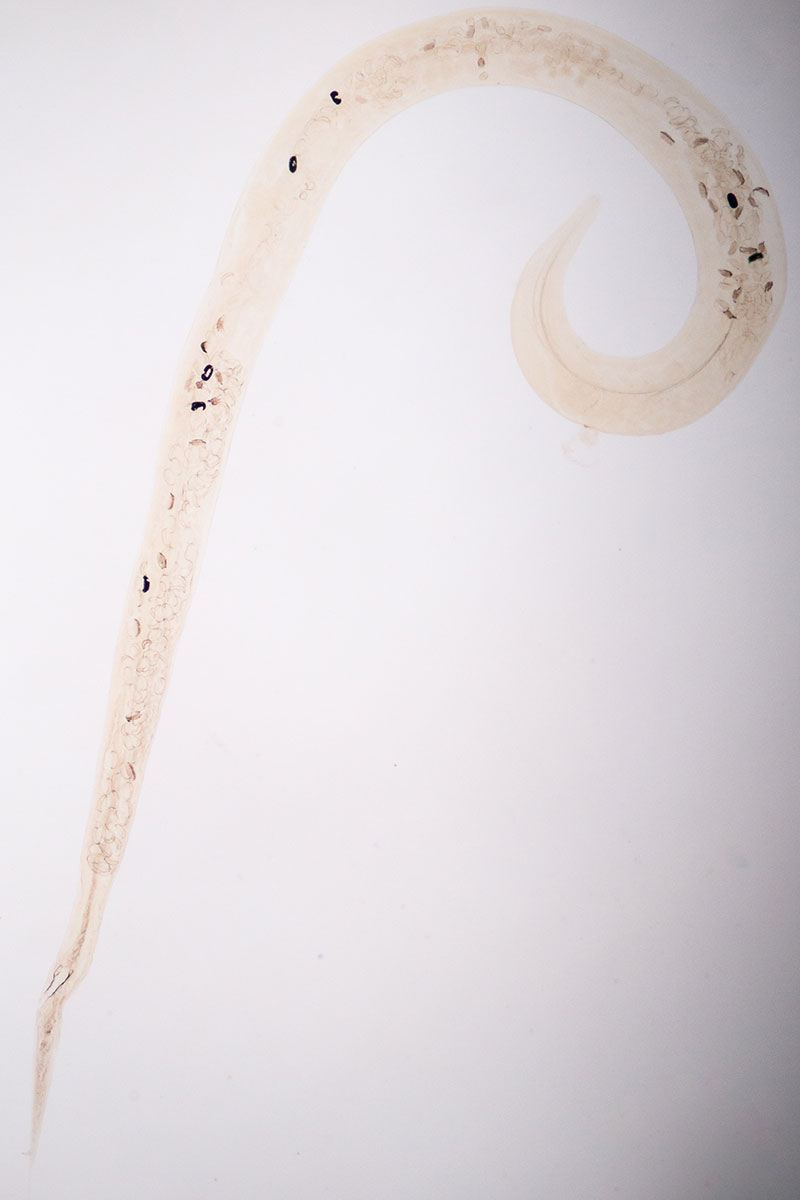

Ascaridia galli

U kur mogą wystąpić różne pasożyty wewnętrzne. Jednymi z nich są glisty – nicienie z rodzaju Ascaridia. U kur spotyka się A. galli, które atakują jelito cienkie ptaków, czasem także grube. Mają żółtobiałe zabarwienie ciała, a w zależności od płci mogą osiągać nawet 120 mm długości. Drób może się zarazić tymi pasożytami poprzez spożycie ze środowiska jaj lub żywiciela paretenicznego (nadprogramowego żywiciela, który nie jest potrzebny do normalnego rozwoju pasożyta), np. dżdżownicy. Glisty uszkadzają błonę śluzową jelit, a także działają toksycznie na organizm ptaka. Przy dużych inwazjach mogą zaczopować światło jelita. Zarażenie A. galli objawia się spadkiem apetytu, wychudzeniem, anemią oraz zahamowaniem wzrostu kurcząt. U chorych ptaków występują biegunki na przemian z zaparciami, pogorszenie jakości upierzenia, a u kur niosek również spadek nieśności. Do zwalczania glist stosuje się przede wszystkim flubendazol. Nie należy go jednak podawać nioskom, od których jaja będą przeznaczone na cele konsumpcyjne. W zwalczaniu Ascaridia skuteczny jest także lewamisol. Najlepiej skonsultować się z lekarzem weterynarii, który ustali dawkowanie leków i sposób ich podania.